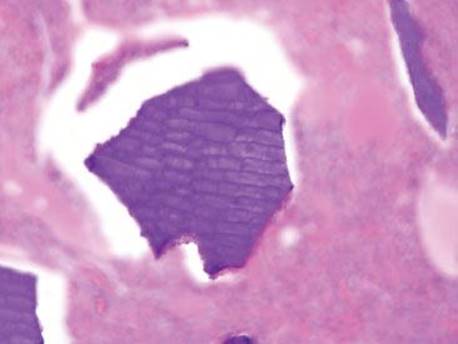

Figure 2.249 Kayexalate. Kayexalate is used in renal failure patients to reduce potassium levels. Importantly, the osmotic effects of the diluent can result in ulcerations and ischemia to the background tissue. The resin is purple on H&E with a characteristic “fish-scale” or “mosaic” appearance due to intersecting “cracking lines”.